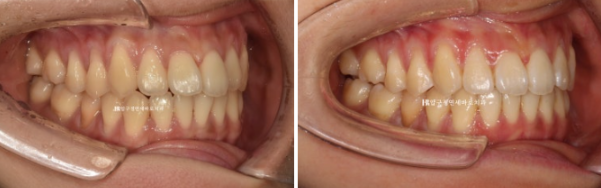

치료 전 - 치료 후 비교 사진입니다.

초진 24.02 이며 치료 종료는 24.07입니다.

24.02~24.07

좋은 교합은 유지가 되었고

토끼이빨은 정상 배열을 찾앗습니다.